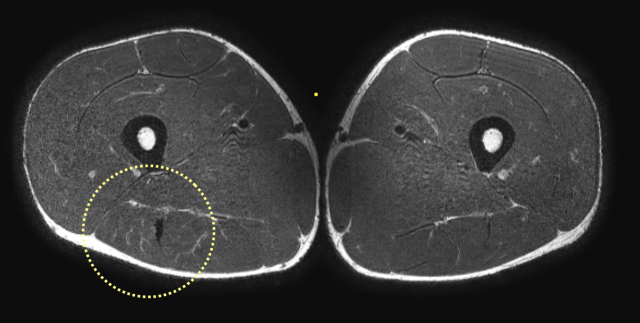

Coronal versus axial

Based on coronal images alone, it is sometimes challenging to exactly classify the amount of distortion. Use the axial images to get a closer look.

On these axial images, high signal and thickening of the left biceps femoris tendon (yellow dotted circle) is seen when compared to the non-injured side (white dotted circle).